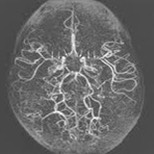

모야모야병은 뇌혈관, 특히 뇌로 혈액을 공급하는 내경동맥과 그 주변 주요 혈관이 점점 좁아지고 막히는 희귀 난치성 질환으로, 혈류가 줄어든 뇌는 부족한 혈액을 보충하기 위해 가느다란 미세측부혈관들을 새로 만들어냅니다. 이 작은 혈관들이 연기처럼 보인다고 하여 일본어로 ‘모야모야(안개·연기)’라는 이름이 붙었습니다. 소아부터 성인까지 폭넓게 나타나며, 특히 5~10세 어린이와 30대 전후의 여성에서 비교적 많이 발견되는 경향이 있습니다. 증상은 일시적 마비, 언어장애, 두통, 실신, 경련 등 매우 다양해 뇌졸중과 유사하거나 초기에는 가벼운 신경학적 증상으로만 나타나 진단이 늦어지기도 했습니다. 질환이 진행하면 허혈성 뇌졸중(뇌경색)이나 출혈성 뇌졸중 위험이 증가하여 반드시 전문적인 관리가 필요합니다. 아직 완전히 예방할 수 있는 방법은 없지만 조기 진단과 적절한 치료를 통해 뇌 기능을 보호하고 삶의 질을 유지할 수 있습니다.

모야모야병은 뇌기저부의 주요 혈관이 서서히 협착되고 막히면서 뇌혈류가 감소하는 만성 진행성 뇌혈관 질환입니다. 협착이 진행된 부위를 대신해 뇌는 생존을 위해 얇고 약한 혈관망을 만들어 혈류를 보충하려 하고, 이 새로운 혈관들이 촬영 영상에서 연기처럼 퍼져 보인다고 하여 ‘모야모야’라는 이름이 붙었습니다. 기전적으로는 내경동맥 말단부와 중대뇌동맥·전대뇌동맥의 기시부에 병변이 가장 잘 생기며, 시간이 지남에 따라 양쪽에 대칭적으로 나타나는 특징을 보였습니다. 이 질환은 단순한 혈관 협착이 아니라 진행성 변화이기 때문에 치료하지 않으면 혈류 부족이 심해지고 뇌 손상이 누적될 수 있습니다. 또한 뇌기능이 체력·호흡·체온 변화 등에 민감하게 반응하기 때문에 과호흡, 울음, 격렬한 운동, 감염 등으로 증상이 악화될 수 있습니다. 즉, 모야모야병은 시간이 지나면서 뇌혈류를 감소시키고 뇌졸중 위험을 높이는 질환이며, 평생 관리가 필요한 만성적 특성을 갖고 있습니다.

따라서 가족력이 있거나 의심되는 증상이 있다면 뇌 MRA·MRI 등의 정기검진이 도움이 되며, 조기 진단 시 치료 효과도 훨씬 높아집니다.